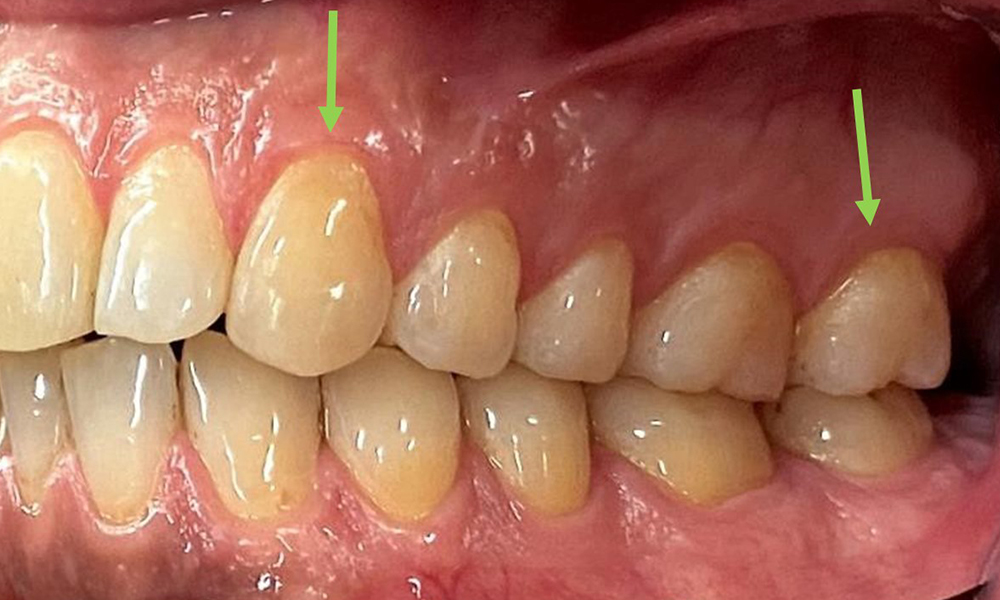

Il n'y a pas eu de résultats pathologiques extra-oraux. Lors de l'examen intrabuccal, l'inspection de la vue frontale a révélé une décoloration brunâtre près de la gencive kératinisée et à la transition vers la muqueuse mobile (Fig. 2), qui pourrait être attribuée à la consommation de nicotine. Des lésions blanchâtres de la muqueuse ont été observées sur le palais, en particulier près des surfaces palatines des molaires maxillaires, ce qui indique une kératinisation accrue et peut également être attribué à la consommation de nicotine. La langue était recouverte d'un enduit amovible blanc et brunâtre.

Entre 1 et 3 mm, les profondeurs de sondage cliniques se situaient dans la plage physiologique. Des récessions maxillaires allant jusqu'à 1 mm ont été observées de la 13 à la 16 et de la 23 à la 27. Le BOP était de 15 %.